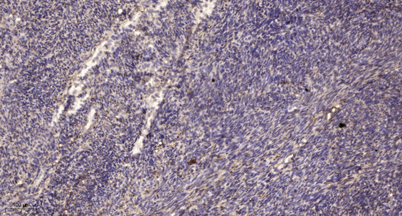

IHC

IHC-p 1:50-300